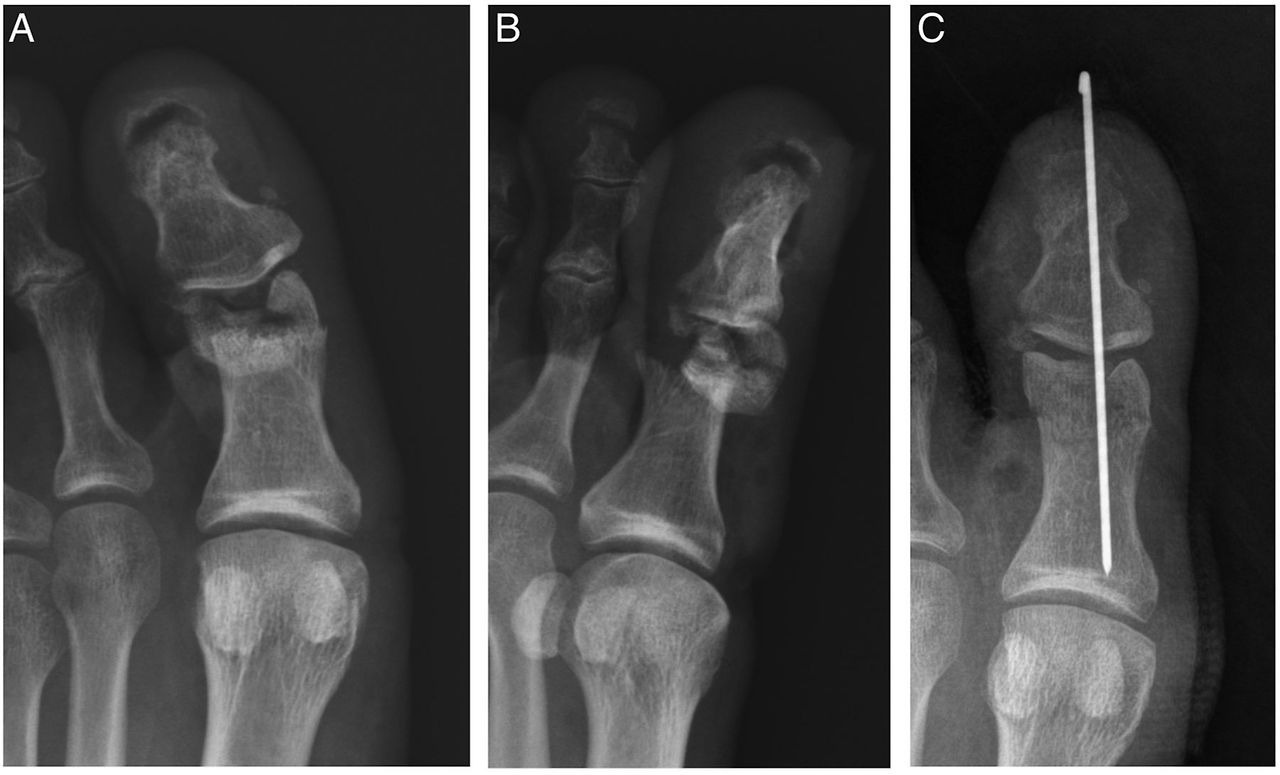

병원에서는 우선 X-ray 촬영을 통해 뼈의 어긋남 여부를 확인한다. 단순 골절이라면 부목 고정이나 깁스로 충분하지만, 뼈가 틀어졌거나 조각난 경우에는 정복술 또는 핀 고정 수술이 필요하다. 치료 과정은 다음과 같이 진행된다.

- 수술: 금속 핀, 나사, 철심을 이용한 내고정술 시행(개방성·분쇄성 골절 등)